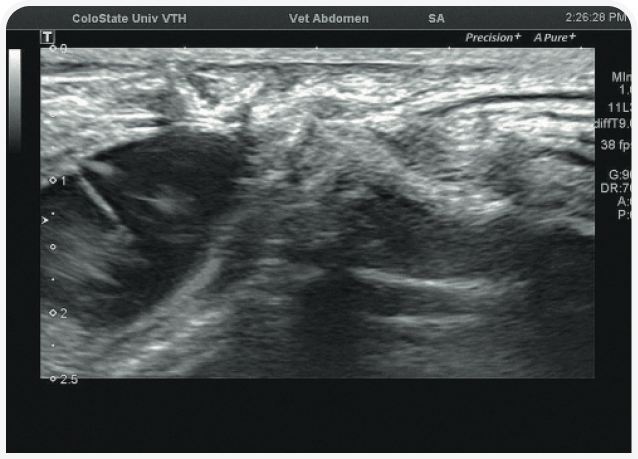

Решающее значение для диагностики и лечения в этом случае будет иметь ультразвуковое исследование органов брюшной полости (Рисунок 6). Диагностику триадита у кошек облегчают визуализация поджелудочной железы и определение толщины/архитектоники стенки кишечника; изменения в паренхиме печени по-прежнему остаются неспецифичными, но изменения в желчном пузыре, скорее всего, помогут установить диагноз. При нейтрофильном холангите у кошки результаты визуализации желчных путей могут оказаться нормальными, но во многих случаях стенка желчного пузыря будет утолщенной и неровной, даже зубчатой (Рисунок 7) (22). Возможны осадок (Рисунок 8) или наличие камней в желчном пузыре, поэтому желчевыводящие пути важно просмотреть до двенадцатиперстной кишки, чтобы исключить внепеченочную окклюзию желчных протоков. Во многих случаях общий желчный проток оказывается перекрыт. Возможен асцит, и в этом случае оправдано проведение аспирации и анализа состава жидкости.

Аспирация содержимого желчного пузыря (чрескожный холецистоцентез под контролем ультразвукового исследования) для цитологического и культурального исследования чаще всего позволяет поставить диагноз и подобрать лечение (Рисунок 9) (23). Если желчный пузырь при визуализации выглядит патологически (например, толщина стенки >1 мм, контур стенки неровный или зубчатый или выраженное гиперэхогенное содержимое (осадок; Рисунок 10), результаты цитологического исследования и бактериального посева, скорее всего, также будут отклоняться от нормы (22,24). Обратите внимание, что при аспирации существует риск разрыва стенки желчного пузыря и/или утечки содержимого с развитием желчного перитонита, но под контролем опытного специалиста УЗИ и при спокойном поведении/седации пациента проблемы возникают редко. Тем не менее если стенка желчного пузыря выглядит эмфизематозной, риск значительно возрастает и вместо аспирации следует рассмотреть возможность хирургического удаления или пробное лечение.